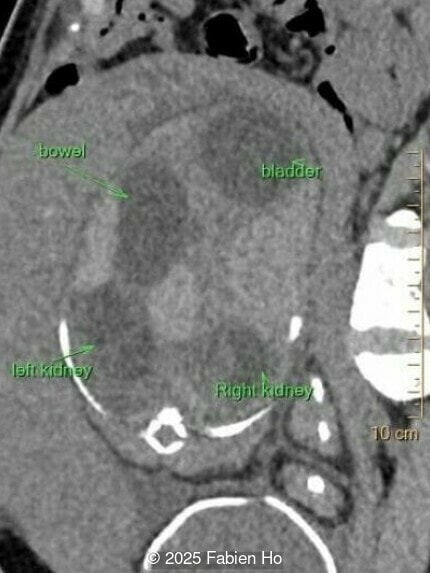

Axial image of the abdomen

Image 7 Axial image of the abdomen

Axial image of the fetal pelvis

Image 14 Axial image of the fetal pelvis

Our prenatal ultrasound revealed a male fetus with megabladder, dilation of both ureter and kidneys, and thinned kidney parenchyma consistent with Lower Urinary Tract Obstruction (LUTO).  Additional findings suspected on ultrasound and confirmed on computed tomography included:

• Dysostosis: Hemivertebrae L3, fused L4-L5, abnormal left foot with short metatarsals and missing phalanges

• Suspicion of dilated bowel in the left flank, in addition to dilated urinary tract